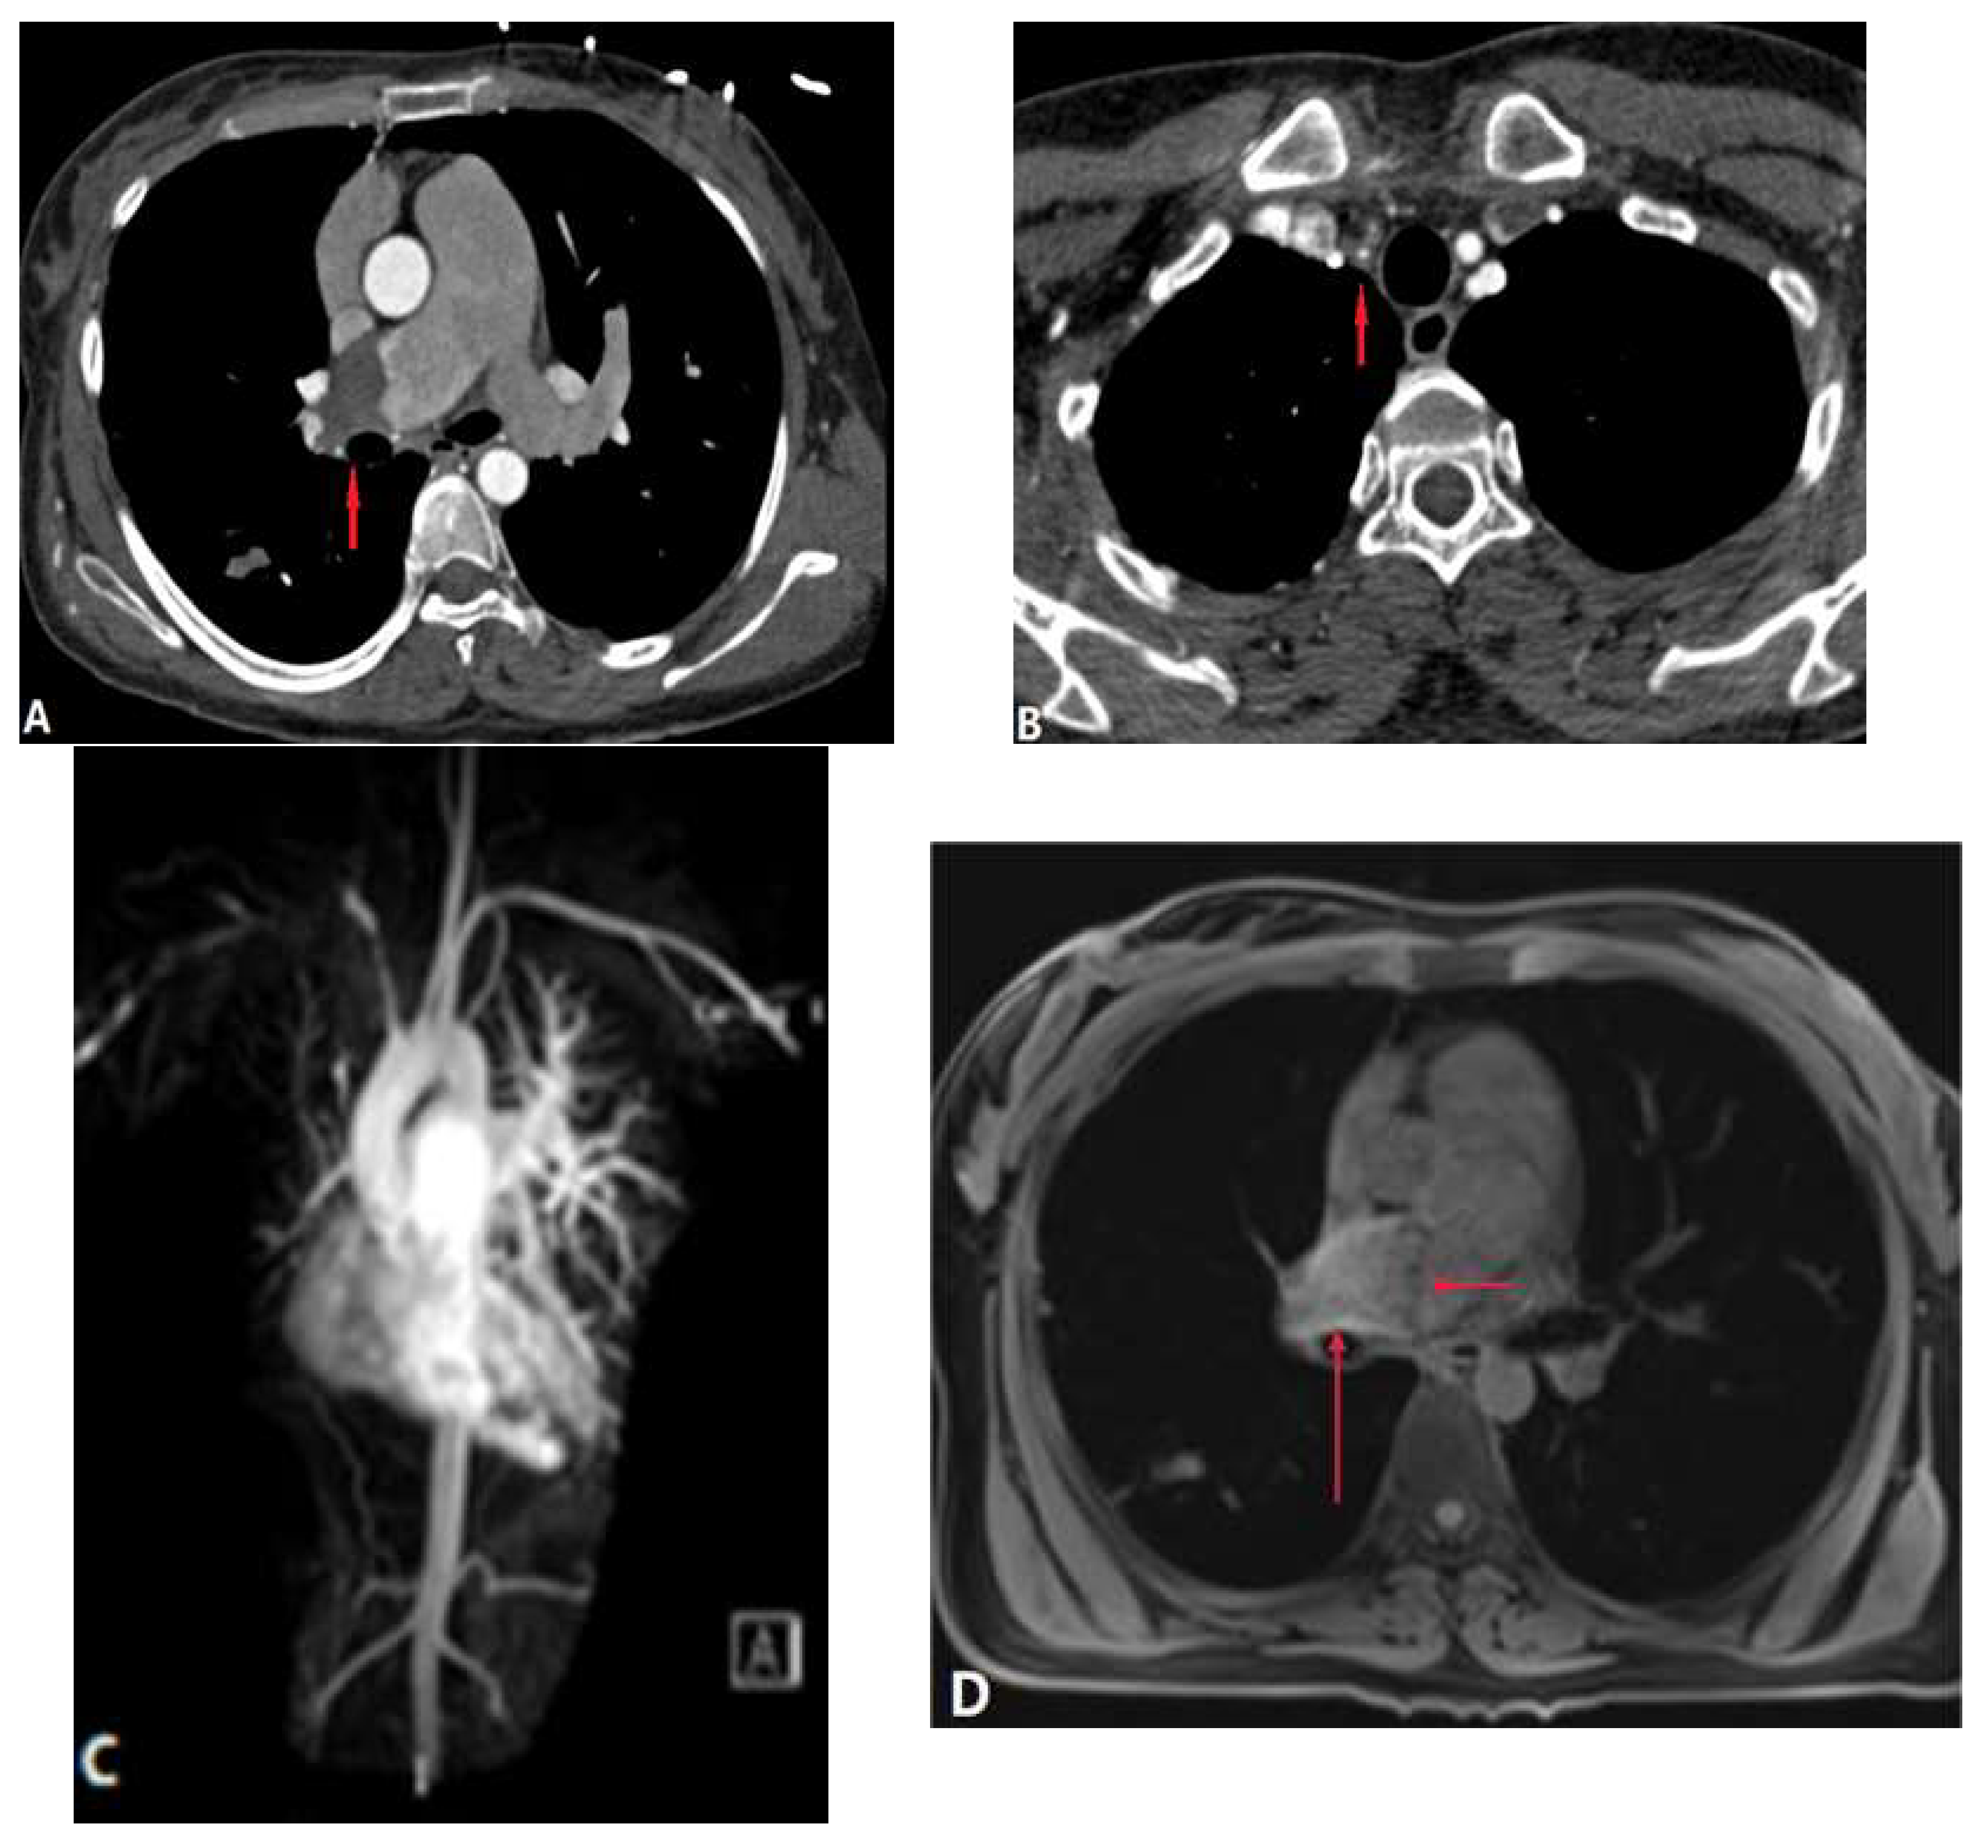

3.3.1. Fibrosis Mediastinitis (FM)

3.3.2. Tumour Causing Pulmonary Artery Stenosis

4. Complications of Radiofrequency Ablation Of Atrial Fibrillation